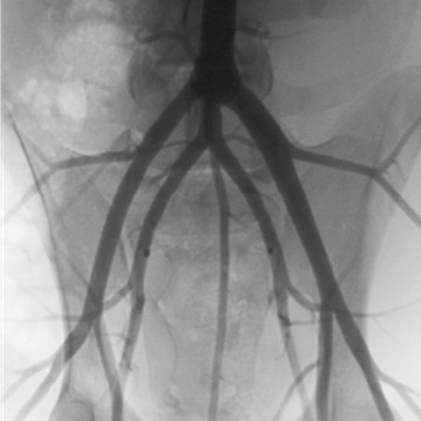

DSA(Digital Subtraction Angiography) helps various clinical diagnosis and procedures through the vessel image information after injecting contrast medium.